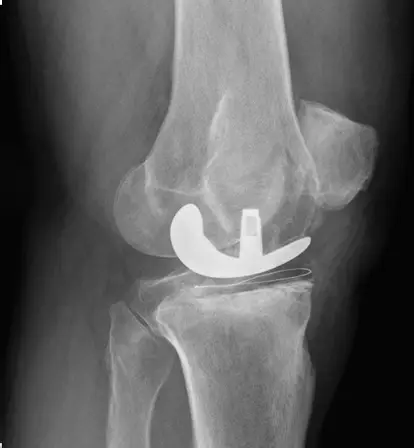

How TKR Surgery Is Performed

TKR surgery involves removing the damaged knee joint surfaces and replacing them with artificial implants that mimic natural movement. Robotic assistance may be used for precise implant alignment, enhancing joint stability and function.

• Accurate implant alignment with robotic assistance

• Restoration of knee stability and function